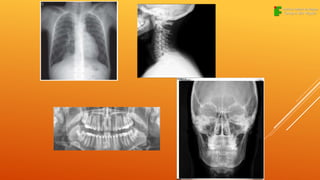

RADIOGRAFIA

A radiografia é uma imagem obtida, após

um feixe de raios X ou

raios gama, atravessa a região de estudo e

interagir com uma emulsão

fotográfica ou tela fluorescente, existe uma

grande variedade de tipos, tamanhos e

técnicas radiográficas.

Radiografia oral

Radiografia de tórax

Radiografia de membros

Radiografia de crânio

Radiografia de cérebro

Radiografia de coluna

RADIOGRAFIA A radiografia éuma imagem obtida, após um feixe de raios X ou raios gama, atravessa a região de estudo e interagir com uma emulsão fotográfica ou tela fluorescente, existe uma grande variedade de tipos, tamanhos e técnicas radiográficas.

Radiografia oral Radiografia detórax Radiografia de membros Radiografia de crânio Radiografia de cérebro Radiografia de coluna